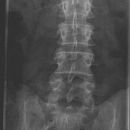

LWS a.p.

Es wurden keine Bilder gefunden.

Kassette/Abstand

Format 20/40 hoch / FFA 1,15m

Lagerung

Patient in Rückenlage, Arme längs des Körpers, durch Unterpolsterung oder Anziehen der Knie, Ausgleich der Lendenlordose. Zur Darstellung der ISF darf das Format nicht eingeblendet werden! Keine Bleischürze - falls möglich Hodenkapsel/Schmetterling

Zentralstrahl

Senkrecht auf WS und oberen hinteren Beckenkamm.

Indikation

Zwischenwirbelraum frei projiziert.

Qualitätskriterien

Scharfe und orthograde Abbildung aller Lendenwirbel mit ihren Querfortsätzen, der Kreuzdarmbeingelenke und des thorakolumbalen Überganges. Die Dornfortsätze sind mittelständig. Zwischenwirbelraum frei projiziert.